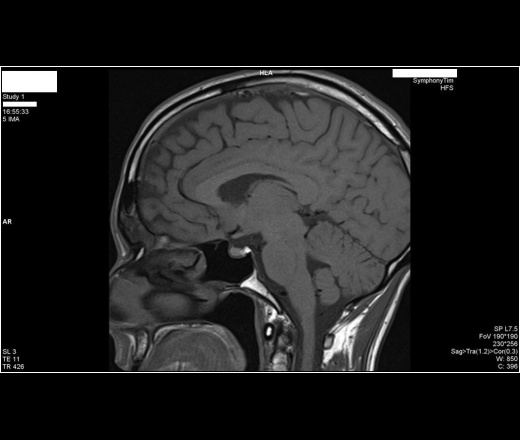

Мужчина 38лет. Обратился с жалобами на утреннюю полиурию, нарушения сна. Пролактин и кортизол в 2 раза превышают норму.

Прошу прокомментировать. (Двойной контур гипофиза на 1-м снимке).

Это не двойной контур гипофиза. Это кортикальные пластинки турецкого седла.

Я бы не сказал, что тут есть какие-либо признаки микроаденомы. В случае сомнения мы всегда делаем отсроченные постконтрастные изображения в хорошем качестве, иногда они помогают больше, чем динамические.

Данных за очаговые изменения гипофиза нет.